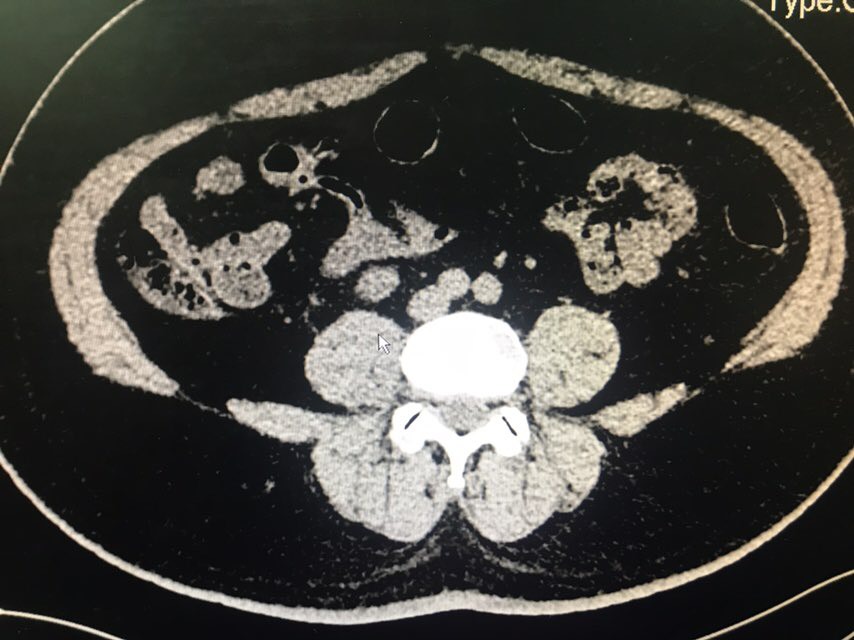

查体:无特殊。辅助检查:全腹CT(我院2018-8-6):右肾盂、肾盏及右输尿管上段明显扩张、积水;右侧输尿管置管。左肾盏区点状结石;双肾囊肿可能。膀胱充盈,壁稍增厚、毛糙,合并炎症可能,胆囊结石。脂肪肝;肝右叶小钙化灶。

从患者CT片子上看,患者右侧输尿管下段狭窄,输尿管支架管返折,因膀胱镜下未能成功取出,故行右侧输尿管探查术。手术顺利,术后给予曲克芦丁脑蛋白水解物注射液5ml治疗,患者术后恢复良好。